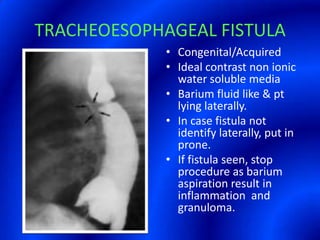

This document provides information about a barium swallow procedure. It begins with an introduction and overview of the embryology and anatomy of the pharynx and esophagus. It then describes the procedure itself, including preparation, technique, views obtained, and indications. Specific conditions that may be examined include pharyngeal and esophageal webs, foreign body impaction, scleroderma, dysphagia, mediastinal masses, and carcinoma. Diagrams are provided to illustrate normal anatomy and various pathological findings.